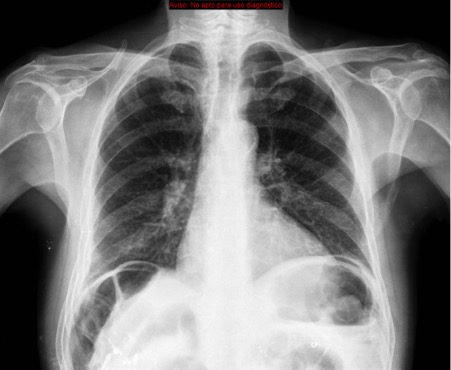

CASO: cáncer de mama. Control anual.

Hallazgos:

- Se observa un aumento de densidad con agrupación broncovascular que produce un borramiento del borde cardicaco derecho; hallazogos compatibles con atelectasia en el lóbulo medio. Véase el TC a continuación: